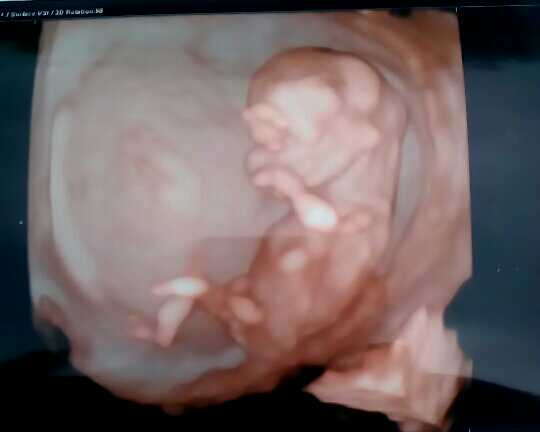

Ahojte holciny tak hlasim ze mam uspesne po skreenngu a jsem absolutne stastna vse je jak ma byt a dokonce nam rekl ze na 60% holcicka coz bych byla stastna kdyz mam 2 kluky doma :-) tak se drzte a prikladam fotecku :-)

I já Péto moc gratuluju k super výsledkům. Miminko je moc krásné. To jsi byla někde v Gennetu, že máš 3D fotku? A o kolik dní ti posunuli termín?